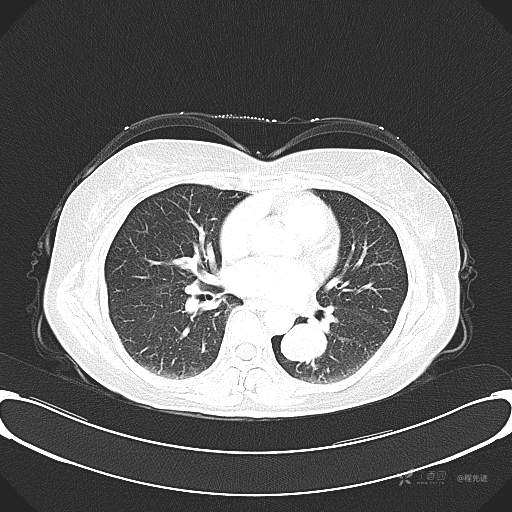

患者性别:女

患者年龄:57岁

简要病史:体检发现

CT增强

平扫CT值约40HU(未上传图像),增强后动脉期CT值约70HU,静脉期CT值约97HU。

肺硬化性血管瘤 (20)